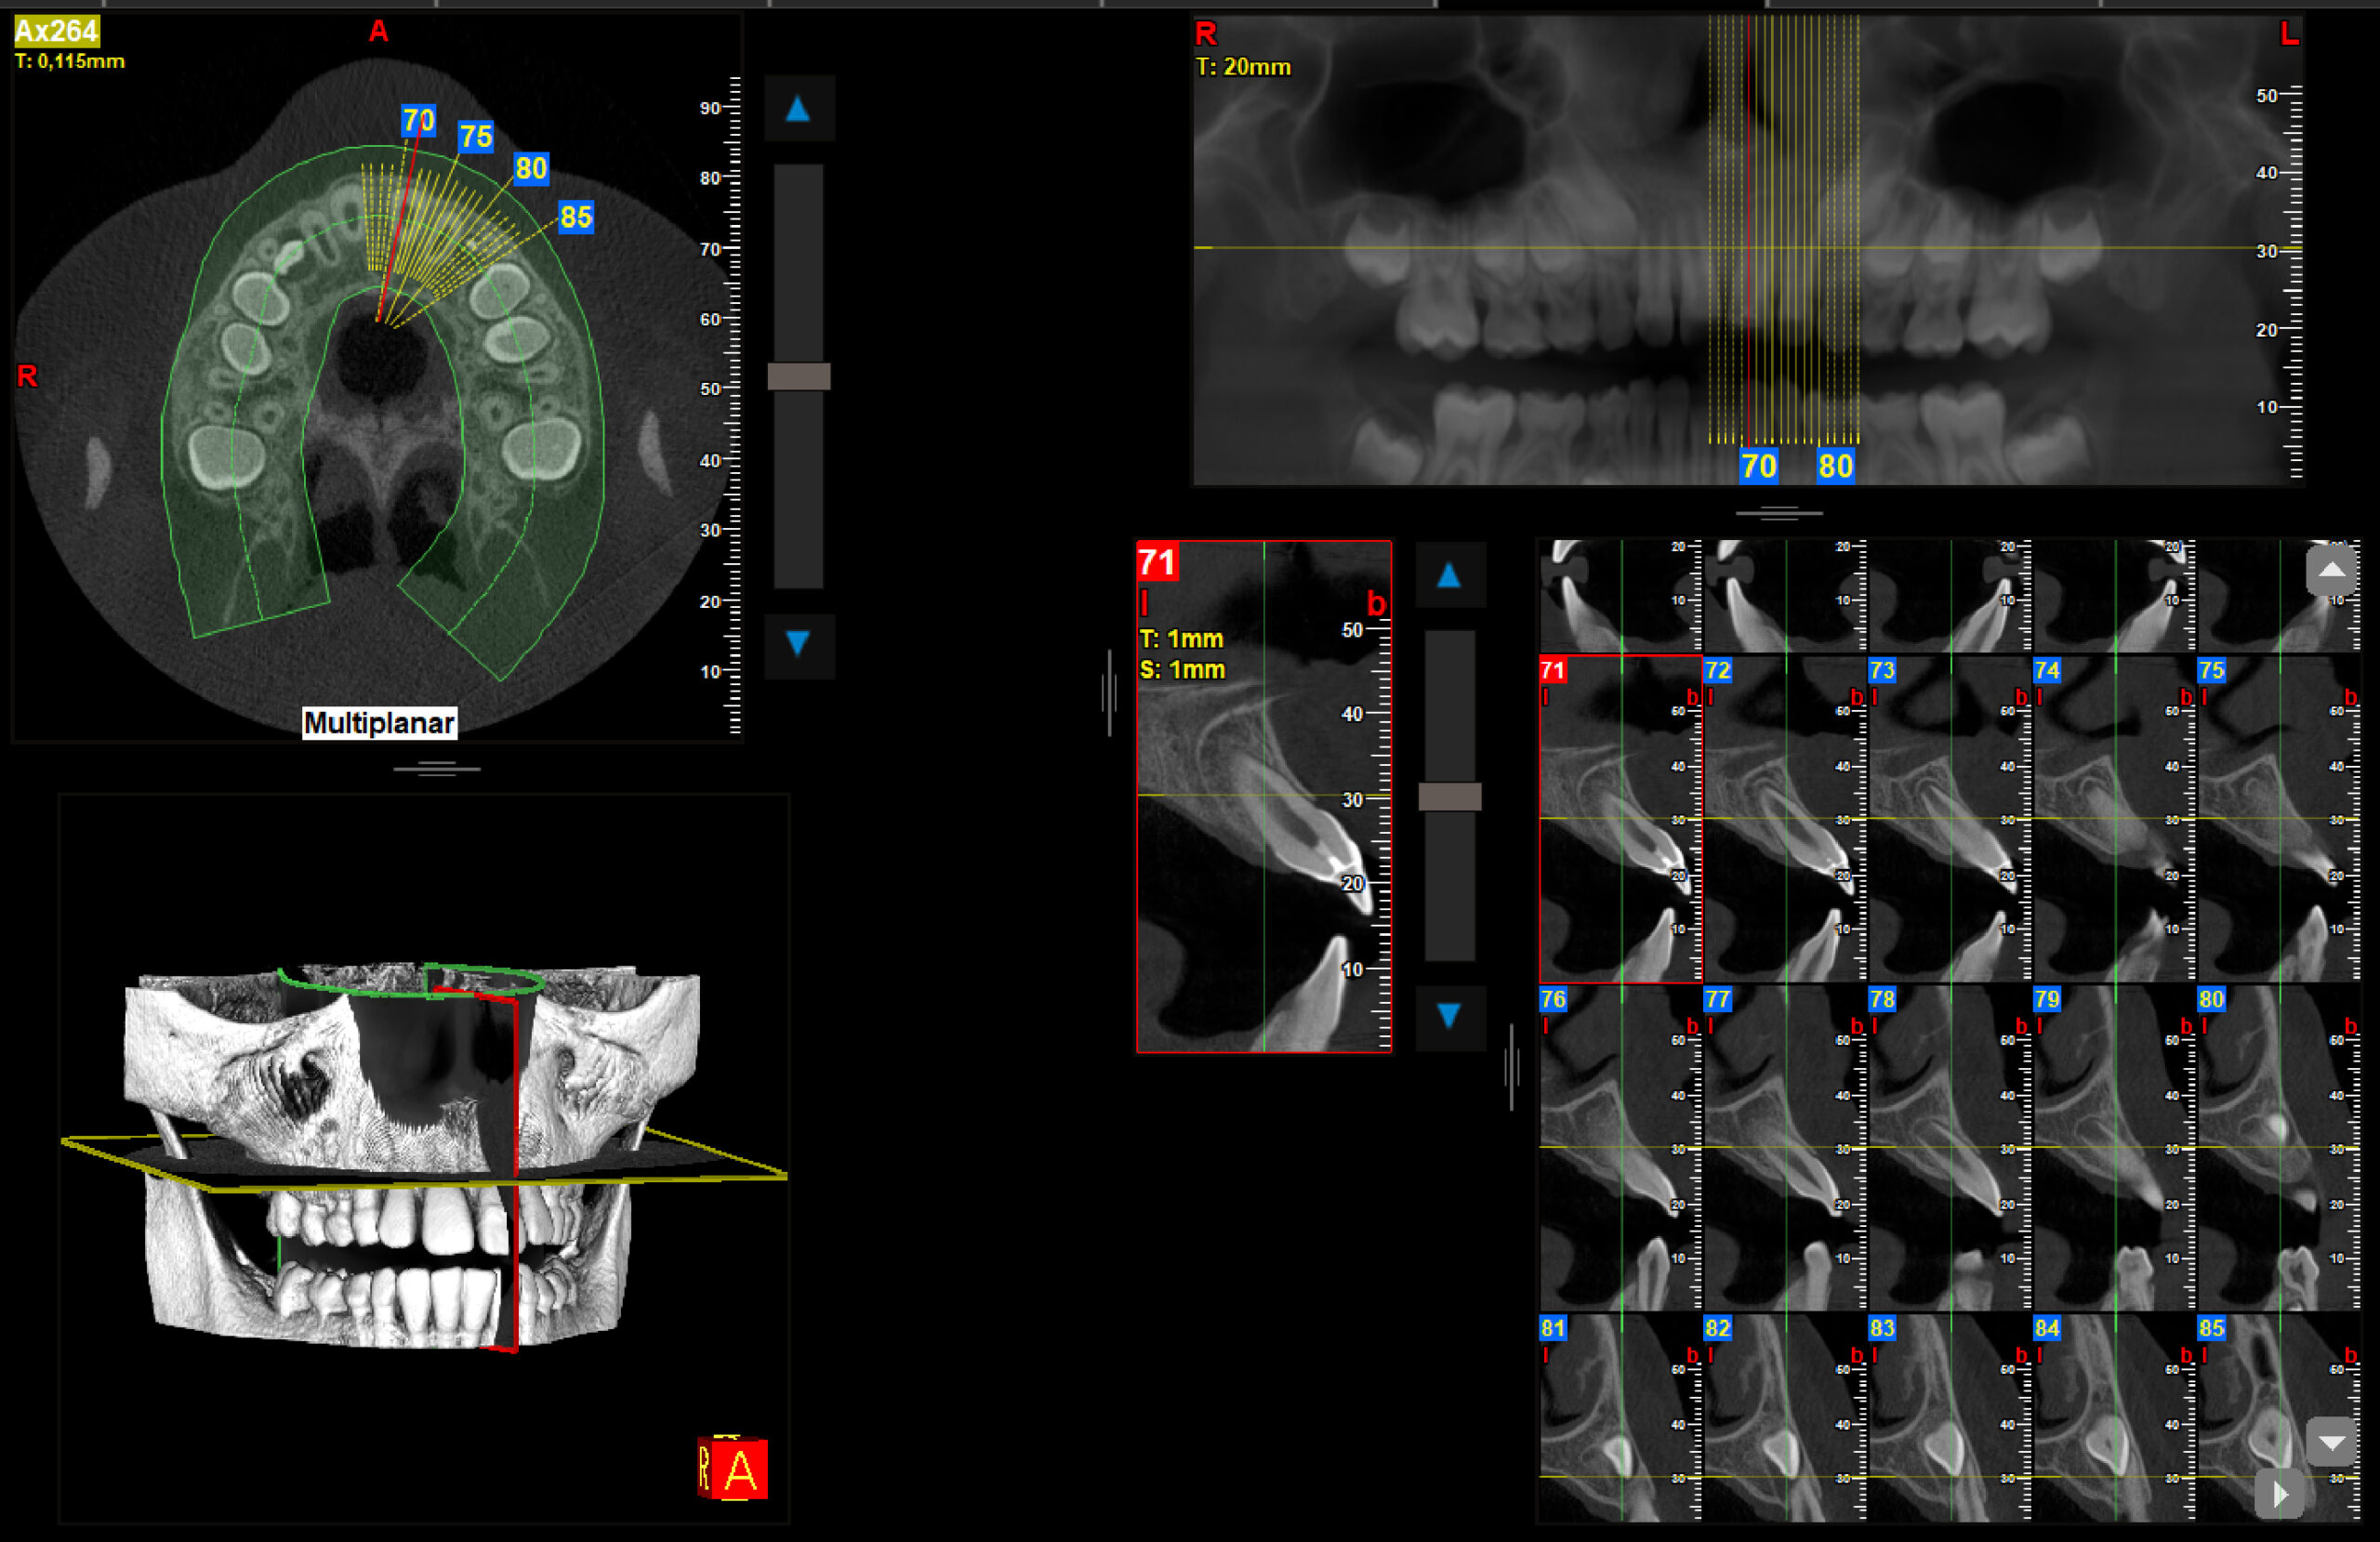

2.1 fractura coronal

Endodoncia y Traumatología Dental

Radiografías